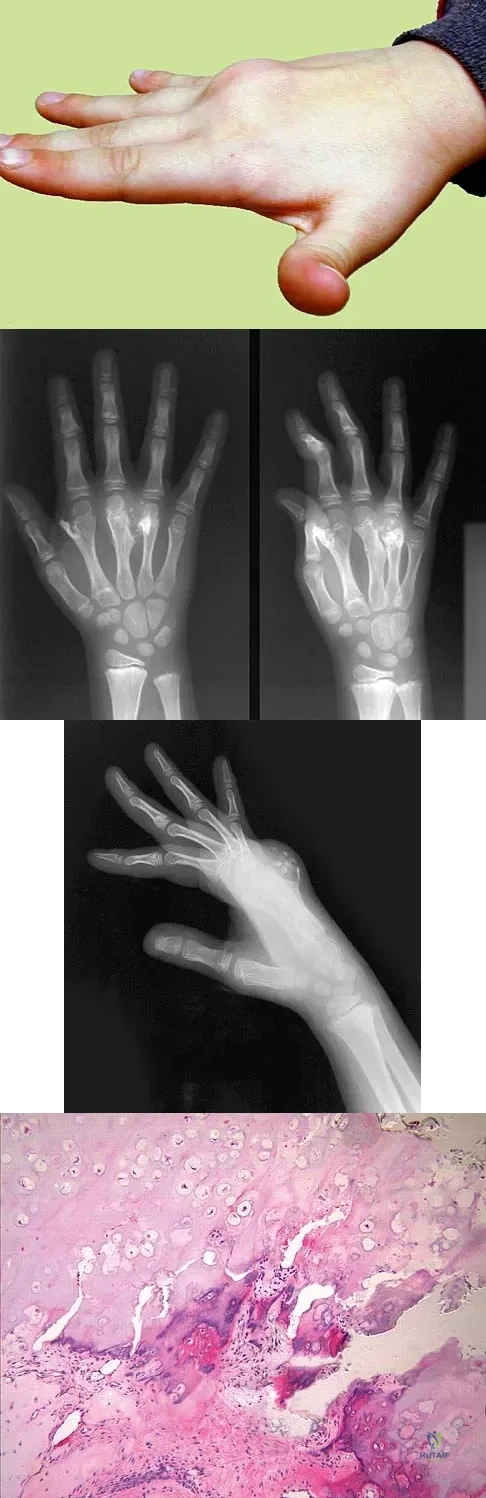

A 9-year-old boy has a painless enlarged mass on the dorsum of his hand. Figures 14a through 14d show the clinical photograph, radiographs, and biopsy specimen. What is the most likely diagnosis?

Explanation